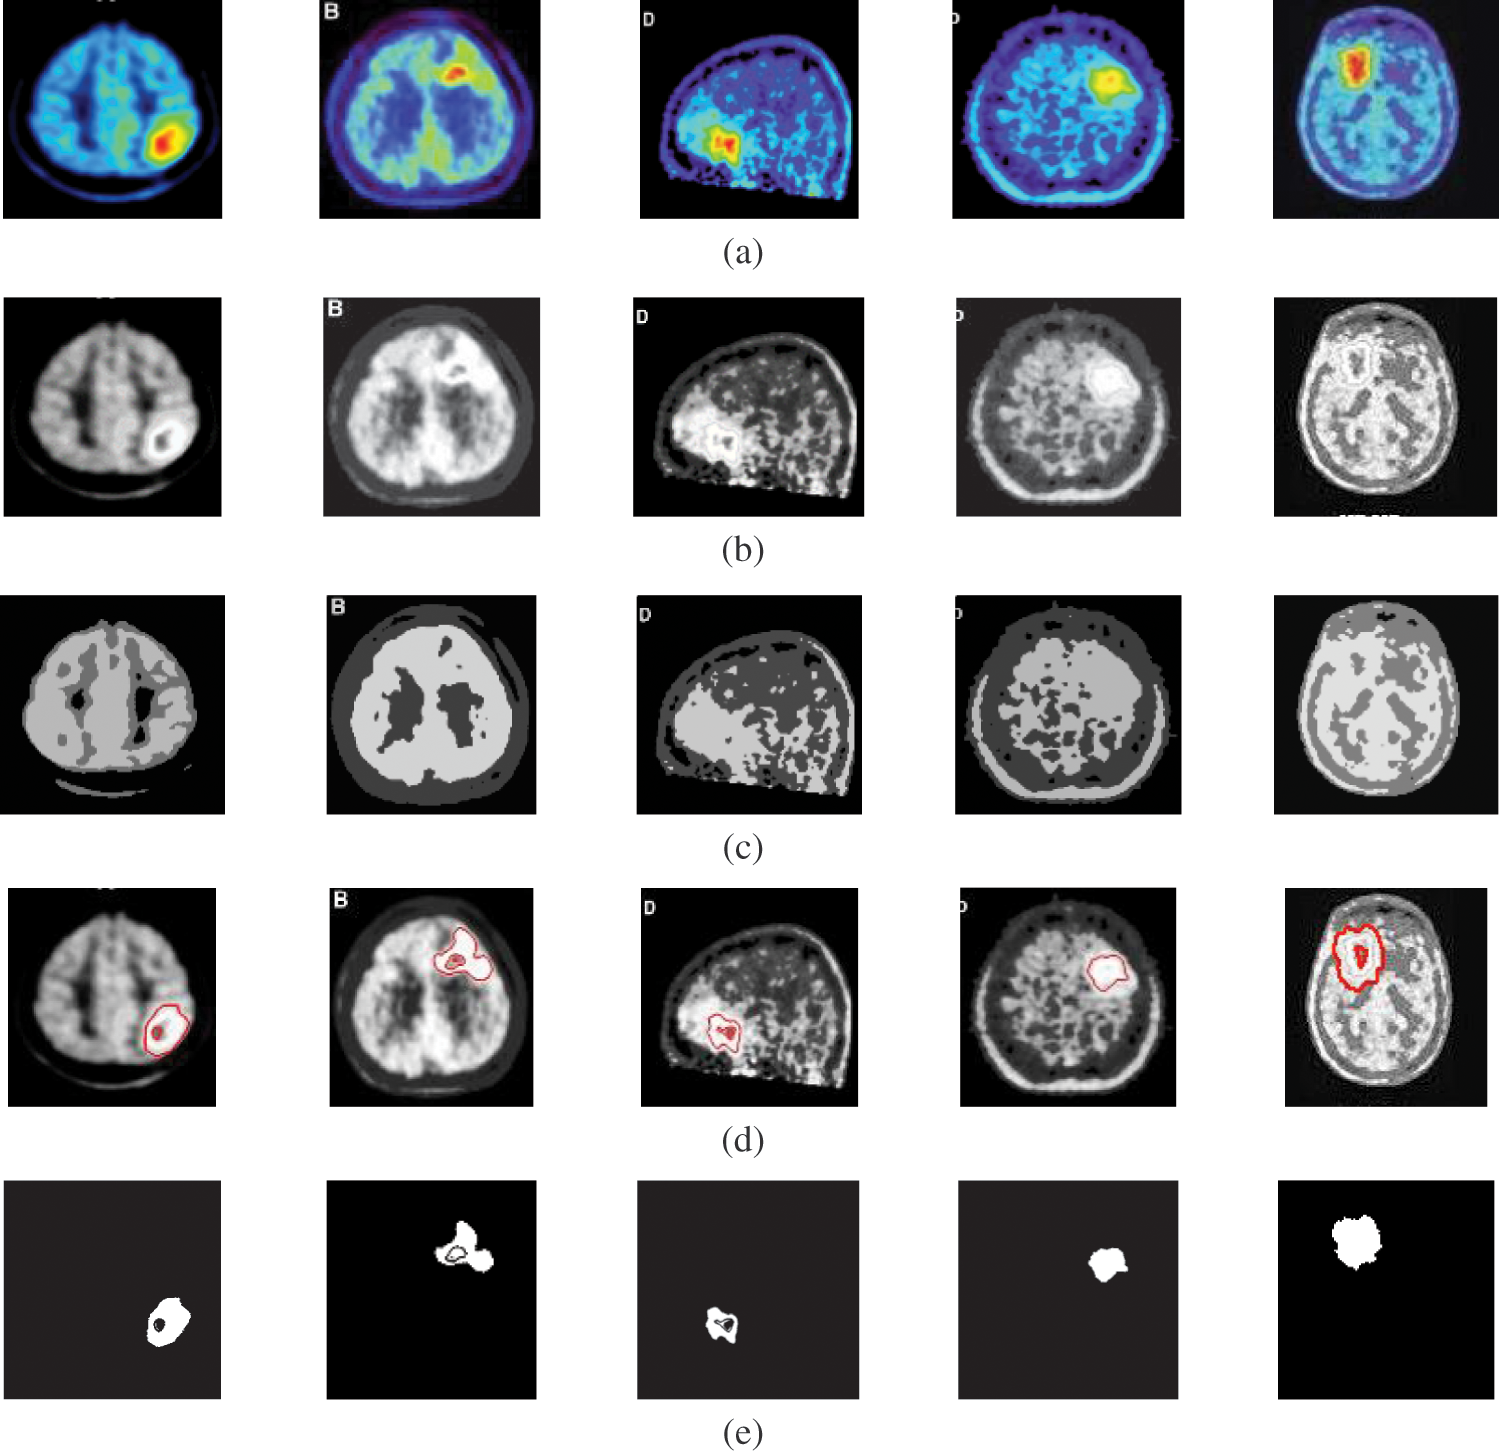

Fig. 2 shows samples of the Us breast images, Fig. 2b shows the Us images after pre-processing stage, Fig. 2c shows the FCM and morphological stage output images, Fig. 2d shows the segmentation results of the ROI produced by active contour model (the tumor is marked by a red contour), and Fig. 2e shows the resultant ROI images. Fig. 3a shows samples of the mammogram original images, Fig. 3b shows the mammogram images after pre-processing stage, Fig. 3c shows the FCM and morphological stage output images, Fig. 3d shows the segmentation results of the ROI produced by the active contour model, and Fig. 3e shows the resultant ROI images. Fig. 4a shows a sample of the CT chest images, Fig. 4b shows the CT images after pre-processing stage, Fig. 4c shows the FCM and morphological stage output images, Fig. 4d shows the segmentation results of the ROI produced by active contour model, and Fig. 4e shows the resultant ROI images.

Fig. 5a shows samples of the PET brain images, Fig. 5b shows the PET images after pre-processing stage, Fig. 5c shows the FCM and morphological stage output images, Fig. 5d shows the segmentation results of the ROI produced by active contour model, and Fig. 5e shows the resultant ROI images. Fig. 6a shows samples of the MRI brain images, Fig. 6b shows the MRI images after pre-processing stage, Fig. 6c shows the FCM and morphological stage output images, Fig. 6d shows the segmentation results of the ROI produced by active contour model, and Fig. 6e shows the resultant ROI images. Tabs. 1–5 show the segmentation Accuracy (Acc.), Sensitivity (Sens.), Precision (Pr.), F-Measure (FM), Matthews Correlation Coefficient (MCC), Dice (D), Jaccard (J), and Specificity (Spec.) numerical results on different image modalities.

Figure 5: A sample of the PET medical images (a) PET images, (b) PET images after preprocessing stage, (c) FCM and morphological operation output images, (d) Segmented images after active contour, and (e) The extracted tumor images

The fourth modality is the PET brain images, shown in Fig. 5. The PET image quality is very low. Firstly, the images are converted into grayscale, and then the proposed approach is applied. The preprocessing step, shown in Fig. 5b, does not improve image quality. Therefore, the segmentation process may not give the desired results. Subsequently, the output of step 3 shown in Fig. 5c, hardly results in good results due to the very low quality of the acquired PET original images. As shown in Figs. 5d and 5e, the active contour model segmentation delineates and extracts the tumor region. The quantitative results for the PET images are given in Tab. 5. The proposed approach can achieve an average segmentation accuracy of 0.9981.